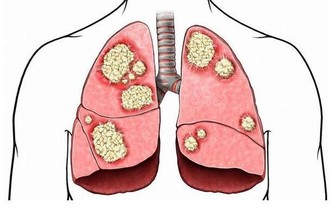

雖然炎症能在受傷的時候保護我們,但大家可能不知道,慢性炎症是非常危險的,它是包括心髒病、癌症在內的致命疾病的誘因。所以,在日常生活中吃一些抗炎食物,不僅可以幫我們減輕炎症帶來的疼痛,也有助於身體健康。

大蒜:殺菌預防胃癌

英國權威醫學雜誌上刊登了一個研究報告,經常吃大蒜能夠降低胃癌的死亡率。我們都知道幽門螺桿菌感染是胃癌的致病因素之一,而經常吃大蒜有助於預防胃癌的發生。因為大蒜中的大蒜素具有一定的殺菌、防癌功效,抑制有利於腫瘤生長的酶活性。所以本身有幽門螺桿菌感染的朋友不妨多吃一些大蒜,能預防胃癌發生。